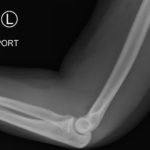

Posterior Elbow Dislocation

A 15-year old female presented with left elbow pain. While competing in a high school wrestling match, she extended her left arm to brace a fall and had immediate onset of sharp pain. She denied weakness or numbness of her left arm. She had no past medical history.

Elbow dislocations are classified by the position of the radio-ulnar joint relative to the humerus.1 Images 1, 2, and 3 show a left posterior elbow dislocation; the radius and ulna are displaced posteriorly with respect to the distal humerus. The lateral view of the elbow most clearly shows this: trochlear notch of the ulna is empty and displaced posteriorly relative to the trochlea. There is no associated fracture. Images 4 and 5 show the elbow status-post reduction, demonstrating proper alignment of the distal humerus with the radius and ulna.

Traumatic dislocations of the elbow are relatively uncommon in pediatric patients, with a peak incidence at 13 to 14 years.1 Dislocations are usually posterior and occur after forced abduction and extension of the elbow.1 It is important to evaluate for an associated fracture or avulsion, which occurs in over 50% of pediatric elbow dislocations. Fractures most commonly involve the medial epicondyle, radial head and neck, or coronoid process.1 One should also consider a neurovascular injury to the ulnar or median nerve or to the brachial artery or its branches.1

Posterior elbow dislocations should be reduced as soon as possible.1 Patients should receive adequate sedation and/or analgesia. One method of reduction is the “puller” technique, during which a practitioner stabilizes the humerus, while a second practitioner applies force against the anterior forearm, with gentle traction distally.1 Post-reduction neurovascular reassessment is important. After successful reduction, patients can be immobilized in a posterior long arm splint.